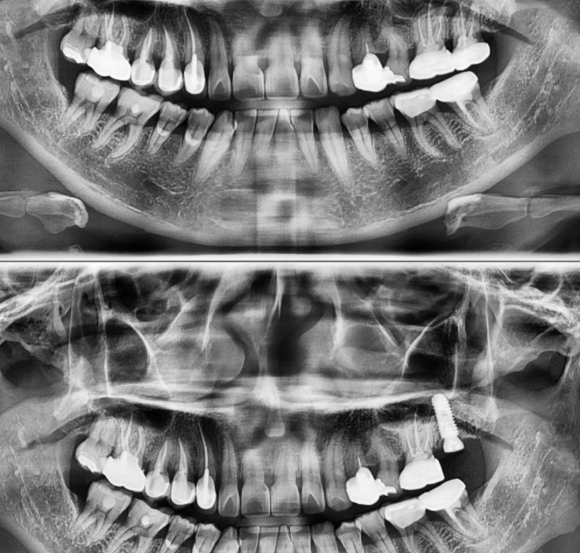

2022.3.5 구치부 발치 후 즉시 임플란트/ 상악동+뼈이식 케이스